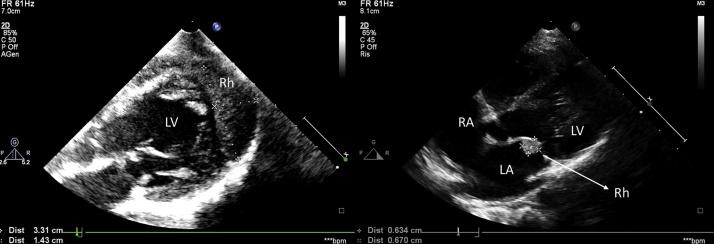

Rhabdomyomas are the most frequent cardiac tumors in children. Furthermore, they are often associated to tuberous sclerosis complex, an autosomal dominant neurocutaneous disorder characterized by tumor-like malformations that involve many organ systems.

We describe a rare ECG pattern in a severe case of neonatal tuberous sclerosis complex.

In the presence of significant rhabdomyomatosis related to tuberous sclerosis, multiple clusters of rhabdomyoma-like cells can infiltrate the myocardium, with increased fibrosis areas.

Considering the fact that rhabdomyomas often show spontaneous regression, close follow-up is sufficient in hemodynamically stable cases. Destruction of the conduction system, with arrhythmias as consequence, can be the presenting feature of diffuse rhabdomyomatosis.